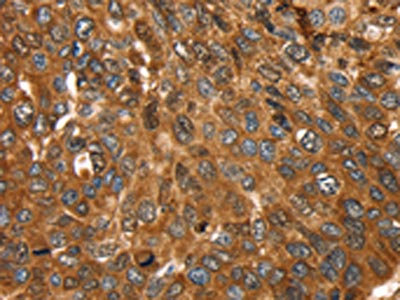

The image on the left is immunohistochemistry of paraffin-embedded Human liver cancer tissue using CSB-PA247700(FTH1 Antibody) at dilution 1/25, on the right is treated with fusion protein. (Original magnification: ×200)

The image on the left is immunohistochemistry of paraffin-embedded Human esophagus cancer tissue using CSB-PA247700(FTH1 Antibody) at dilution 1/25, on the right is treated with fusion protein. (Original magnification: ×200)